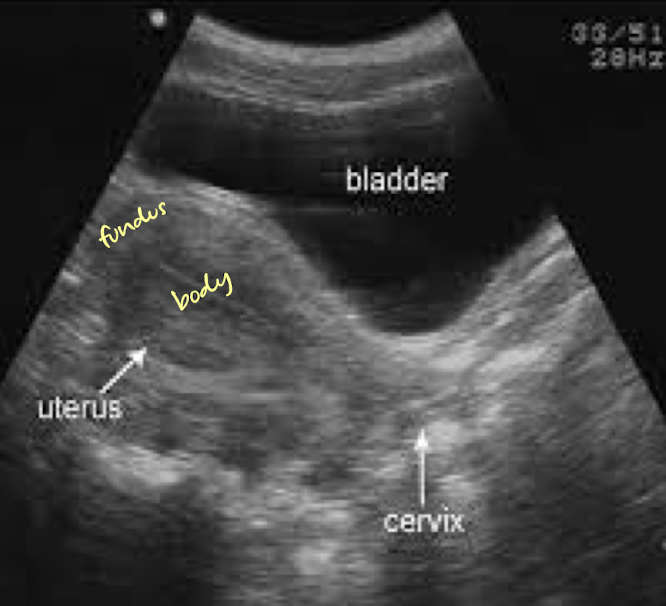

SONO: vagina, cervix, uterus

uterus

located in lesser (true) pelvis

posterior to bladder in vesicouterine pouch

anterior to colon/rectum in rectouterine pouch (aka Pouch of Douglas)

uterus anatomy

thick walled, pear-shaped, muscular organ

3 major sections:

fundus

body

cervix